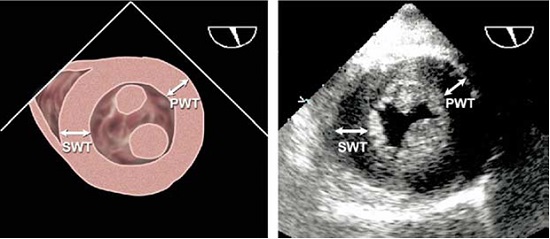

Поперечні розміри ЛШ, товщина МШП та ЗСЛЖ вимірюються в кінці діастоли та систоли в В- чи М-режимі [1,2], бажано в декількох кардіальних циклах [1,2] (Рис. 1). Технічні удосконалення в обробці зображення дозволили поліпшити розрішення кардіальних структур. Тому сьогодні можливо вимірювати безпосередню товщину міжшлуночкової перегородки та інші виміри камер та структур, що визначається, як справжній кордон між тканиною та кров’ю, а не відстань між крайовими ехо-сигналами, як рекомендувалося раніше [5]. Використання лінійних вимірів в В-режимі дозволяє подолати звичайну проблему неперпендикулярних косих вимірів поперечних розмірів структур та камер в М-режимі, що призводять до переоцінки величин розмірів порожнин та товщини стінок.

Рис. 1. Вимір кінцево-діастолічного (КДР) – великий розмір, та кінцево-систолічного (КСР) – маленький розмір – діаметрів ЛШ в М-режимі під контролем В-режиму в парастернальному доступі по короткій вісі ЛШ для оптимізації медіально-латерального позиціонування курсору променя.